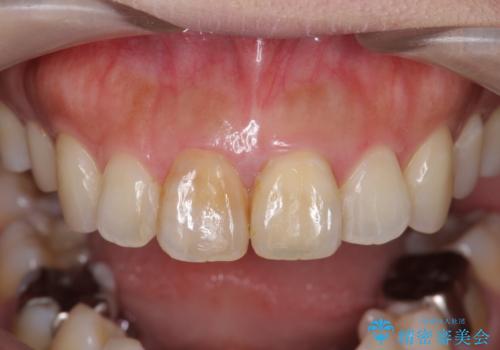

- 歯の神経を除去したのちの、変色の改善を希望され来院されました。

色調の再現に優れるオールセラミッククラウン スペシャルプランでの治療を希望されました。(保証5年間)

天然歯を再現したリアルな仕上がりに満足いただくことができました。

オールセラミッククラウン スペシャルプランは細やかな色調の再現に優れ、目立つ前歯の審美的な仕上がりがより達成されやすいプランです。